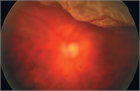

病態

1. 角膜、水晶体、中間透光体、眼底のみならず視神経から後頭葉に及ぶ視路を障害する疾患で視力低下が起こり得る。